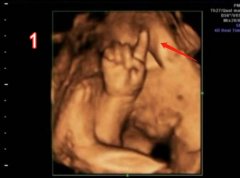

四维彩超(相关四维彩超专题知识分享)